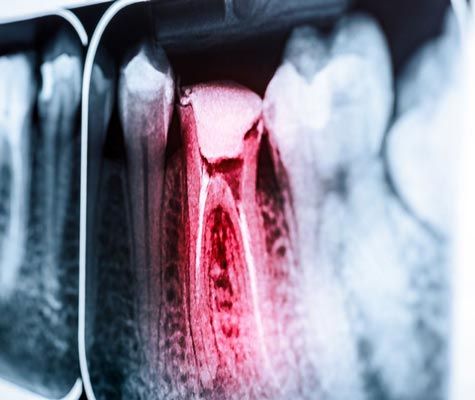

Before a tooth can receive a dental crown, it usually requires some degree of preparation. That might involve simple x-rays, or the tooth may need a root canal. Preparatory treatments will increase the overall cost of your dental care. Furthermore, if you are replacing a lost tooth with a dental implant, your treatment costs will be higher.